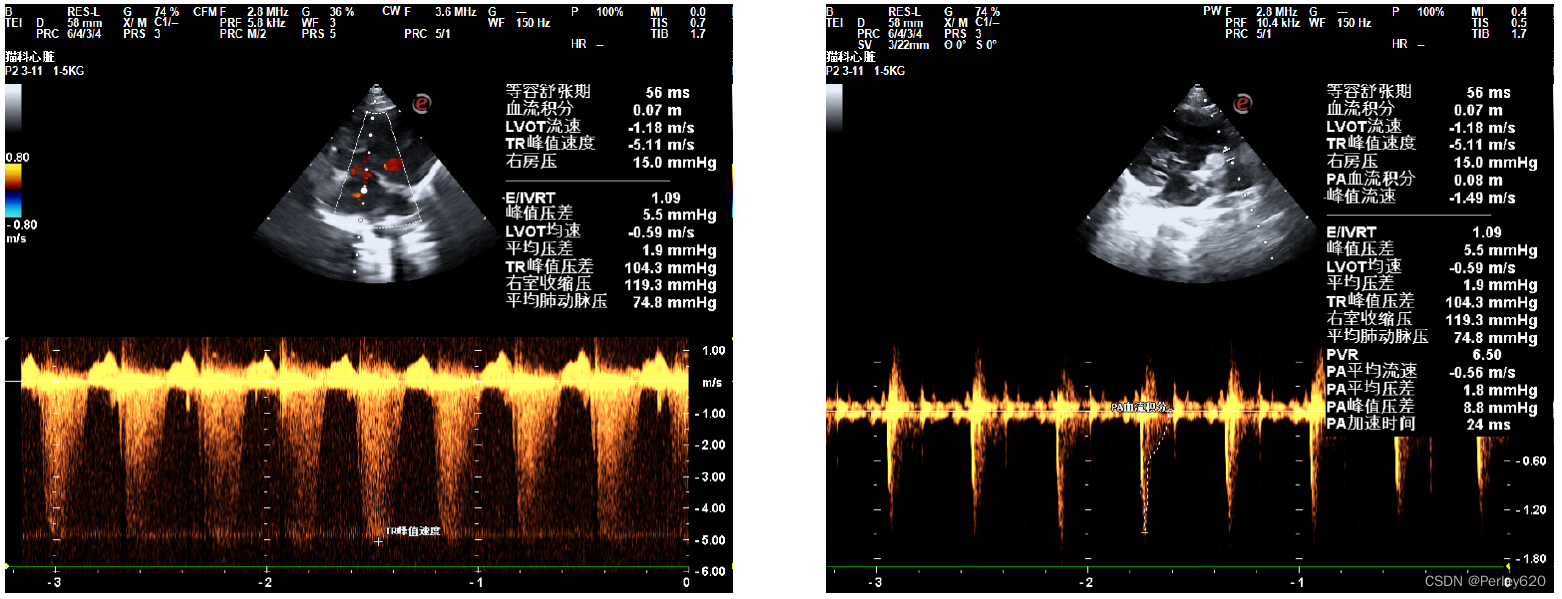

然后给她拍X光片,给她做彩超看心脏,宠物医院的院长看了半天,也没能确定是什么问题,她觉得是心脏左心室隔膜缺损,但没法给定论。

我们就去了宠物医院的总院,找了总院的院长做进一步的检查,最终是重度肺高压,就是很严重的一种病。

诊断的B超图